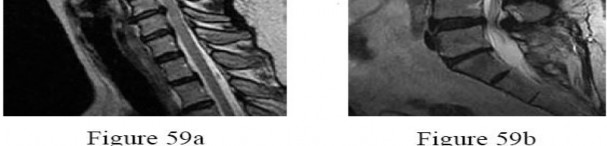

A 65-year-old man presents with progressive clumsiness in his hands, difficulty buttoning his shirt, and a broad-based gait. A T2-weighted MRI shows spinal cord compression with intrinsic cord signal change at C4-C5.

Which of the following MRI findings is associated with the poorest prognosis for neurological recovery after surgical decompression in cervical spondylotic myelopathy?

Explanation

In cervical spondylotic myelopathy, the presence of T1 hypointensity corresponding to a T2 hyperintense lesion indicates myelomalacia or cystic necrosis of the spinal cord. This finding is a strong predictor of poor functional recovery following surgical decompression.